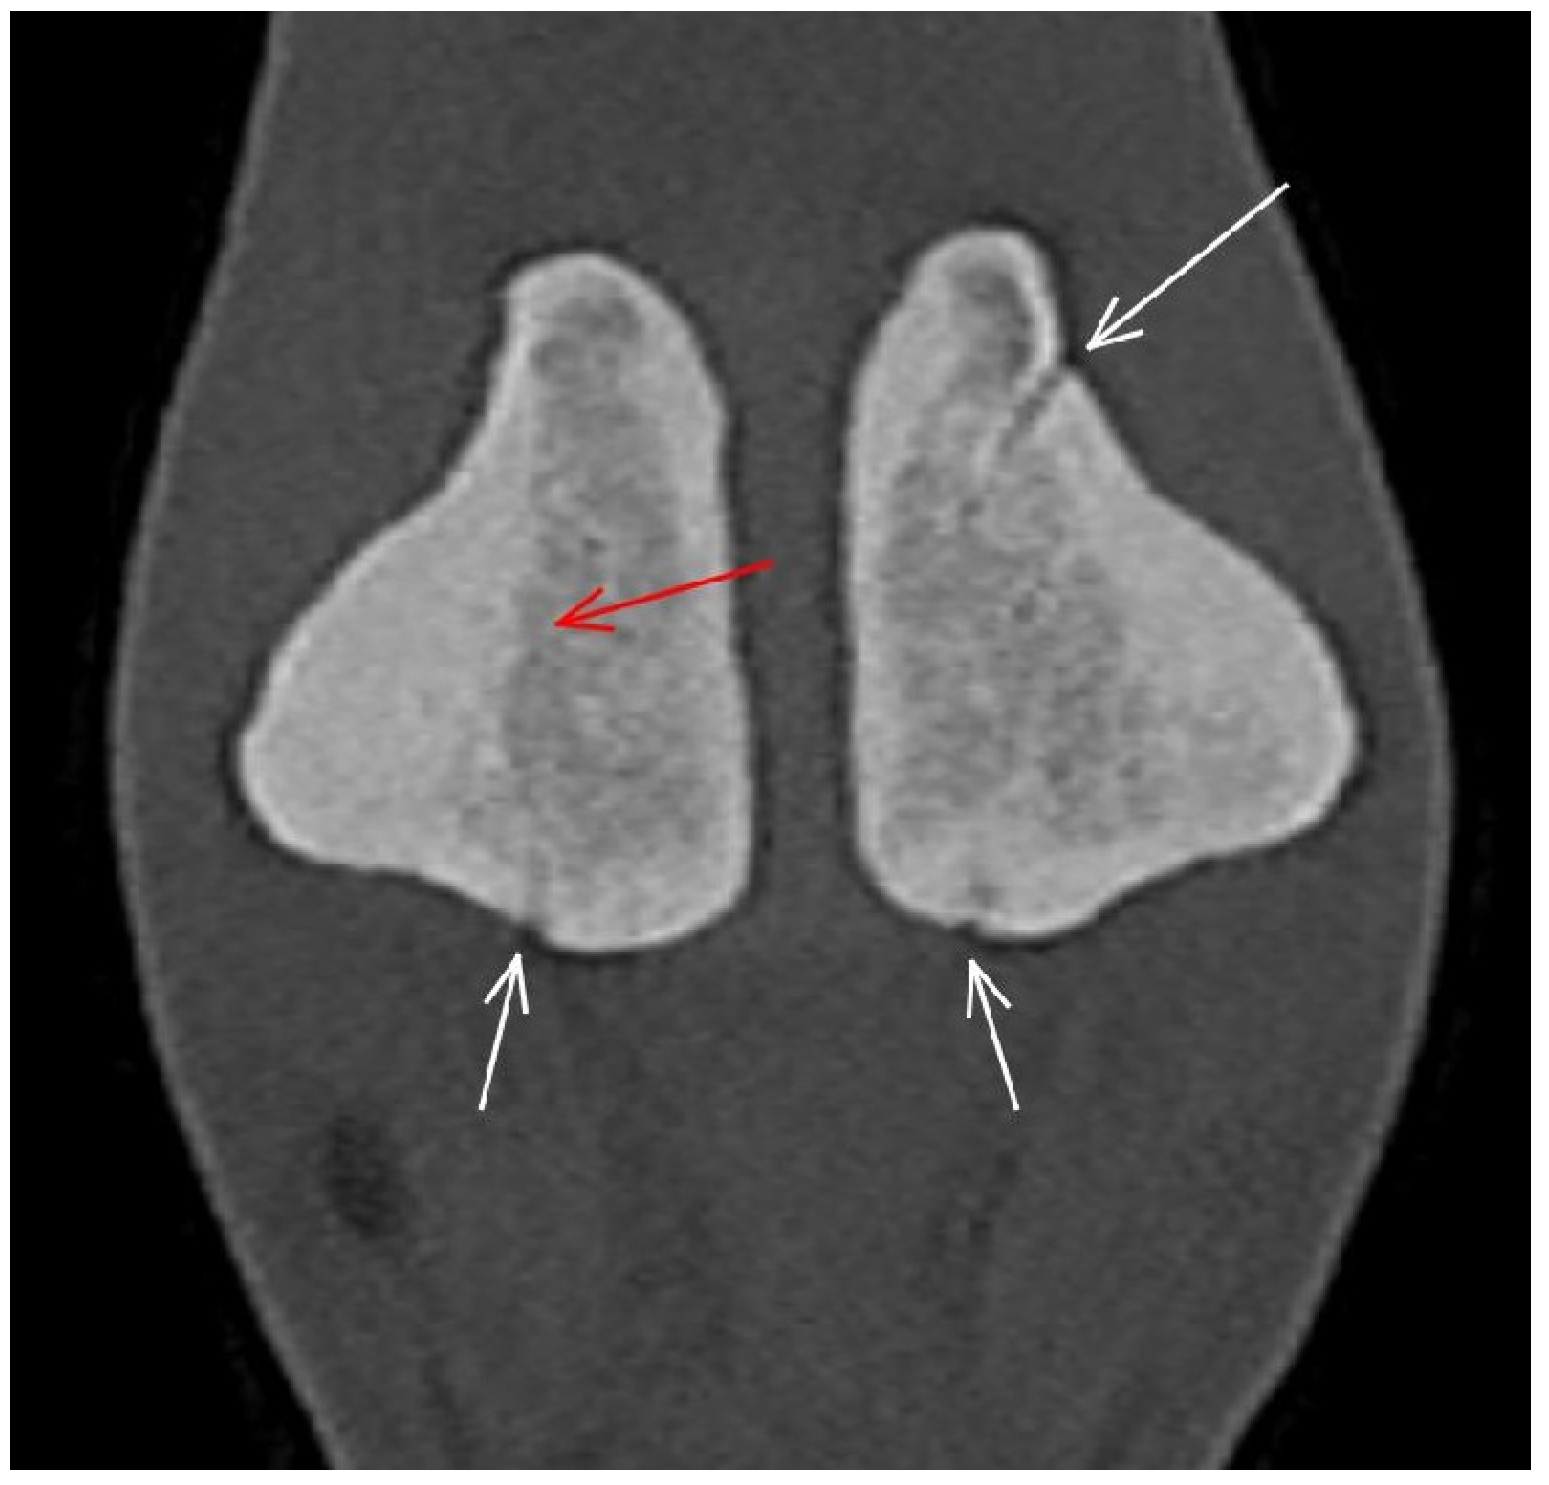

| Proximal sesamoid bone Medial/Lateral | |||

| Prominent vascular channels Thickening of axial/abaxial compact bone Increased attenuation in trabecular bone Modelling | Thickening of axial/abaxial compact bone Decreased signal intensity in trabecular bone Modelling | Prominent vascular channels Modelling | |